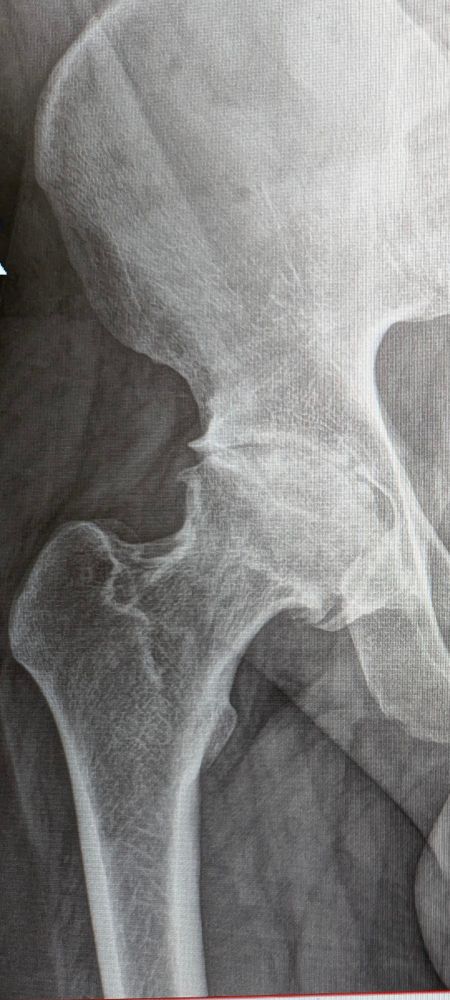

Got home today and recovery is looking swift so far. Here's a comparison my surgeon was able to get for me.

January 13, 2025 at 6:01 PM

As 2025 approached I was greeted with some good news that after 9 years of chronic pain I'm finally getting my hip replacement surgery on the 10th Jan.

Still having a hard time believing it's real but I can barely contain myself.